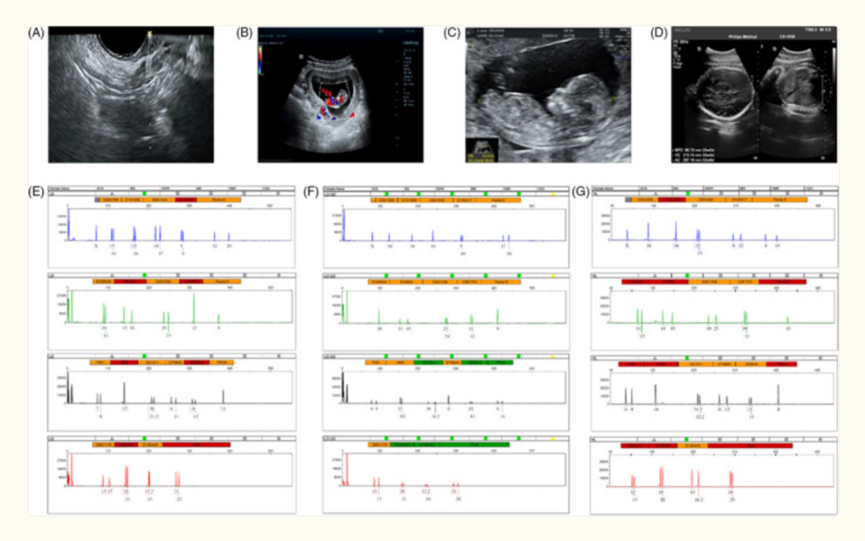

图片来自文献1

目前全球范围内,已经有多项涉及人类受试者的临床研究。以下表格摘取了部分干细胞治疗卵巢早衰的临床试验汇总了所使用的给药途径、细胞剂量以及临床主要观察结果,总共涉及到150余名患者。

研究人员选取了包括促卵泡激素 (FSH)、怀孕和活产次数、雌二醇 (E2)、卵泡计数和卵巢重量等作为判断卵巢功能恢复的可靠预测指标,并且发现,在干细胞疗法治疗后,这些指标存在着明显改善。

在一项来自Sonia Herraiz等人的研究中[3],研究人员选取了 17 名卵巢储备不良的女性作为研究对象。他们采用了一种特殊的方法,在这些女性的一侧卵巢输注了自身来源的干细胞,而另一侧卵巢则不进行输入,作为对照。

注射干细胞后,大部分患者卵巢功能都得到了明显改善

在接下来的观察中,出现了令人惊喜的结果。在注入干细胞的患者中,有多达 13 名(占比 81.3%)患者的卵巢功能都得到了明显的改善。其中,有两个重要的指标可以反映卵巢功能,一个是卵巢窦卵泡计数(AFC),另一个是抗苗勒氏管激素(AMH)水平。在这些患者输入干细胞后的 15 天左右,这两个指标就出现了明显的增加。

而且,这种改善不仅仅体现在这两个指标上。与之前的周期相比,这些患者在术后卵母细胞采集成功率、MII 卵母细胞获得率和胚胎获得率也都明显提高了。这意味着她们的生育能力在多个方面都得到了增强。

最终,在这些女性患者中,一共出现了 5 次妊娠,甚至有 3 名健康婴儿成功出生。这对于卵巢储备不良的女性来说,无疑是一个巨大的福音。